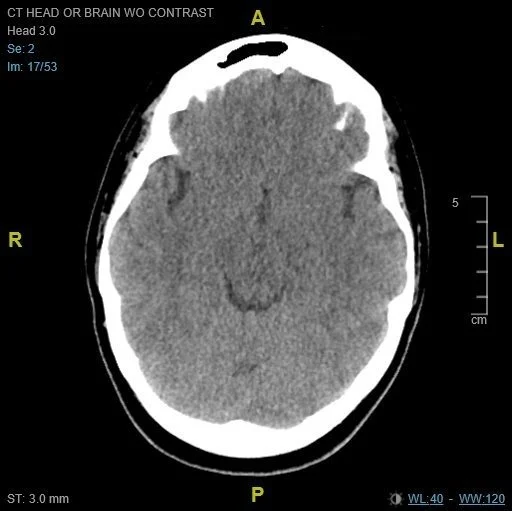

CT Head Radiology Impression:

“1. Focal subarachnoid hemorrhage in the posterior left frontal lobe.

2. Low-density in the occipital lobes bilaterally may represent cortical contusions, ischemic infarctions, or encephalopathy. Recommend MRI for further evaluation.”

A CT of the head demonstrated a small subarachnoid hemorrhage in the left frontal lobe with multiple occipital infarcts bilaterally. A CTA head/neck obtained was grossly unremarkable for aneurysm or other vascular abnormality.